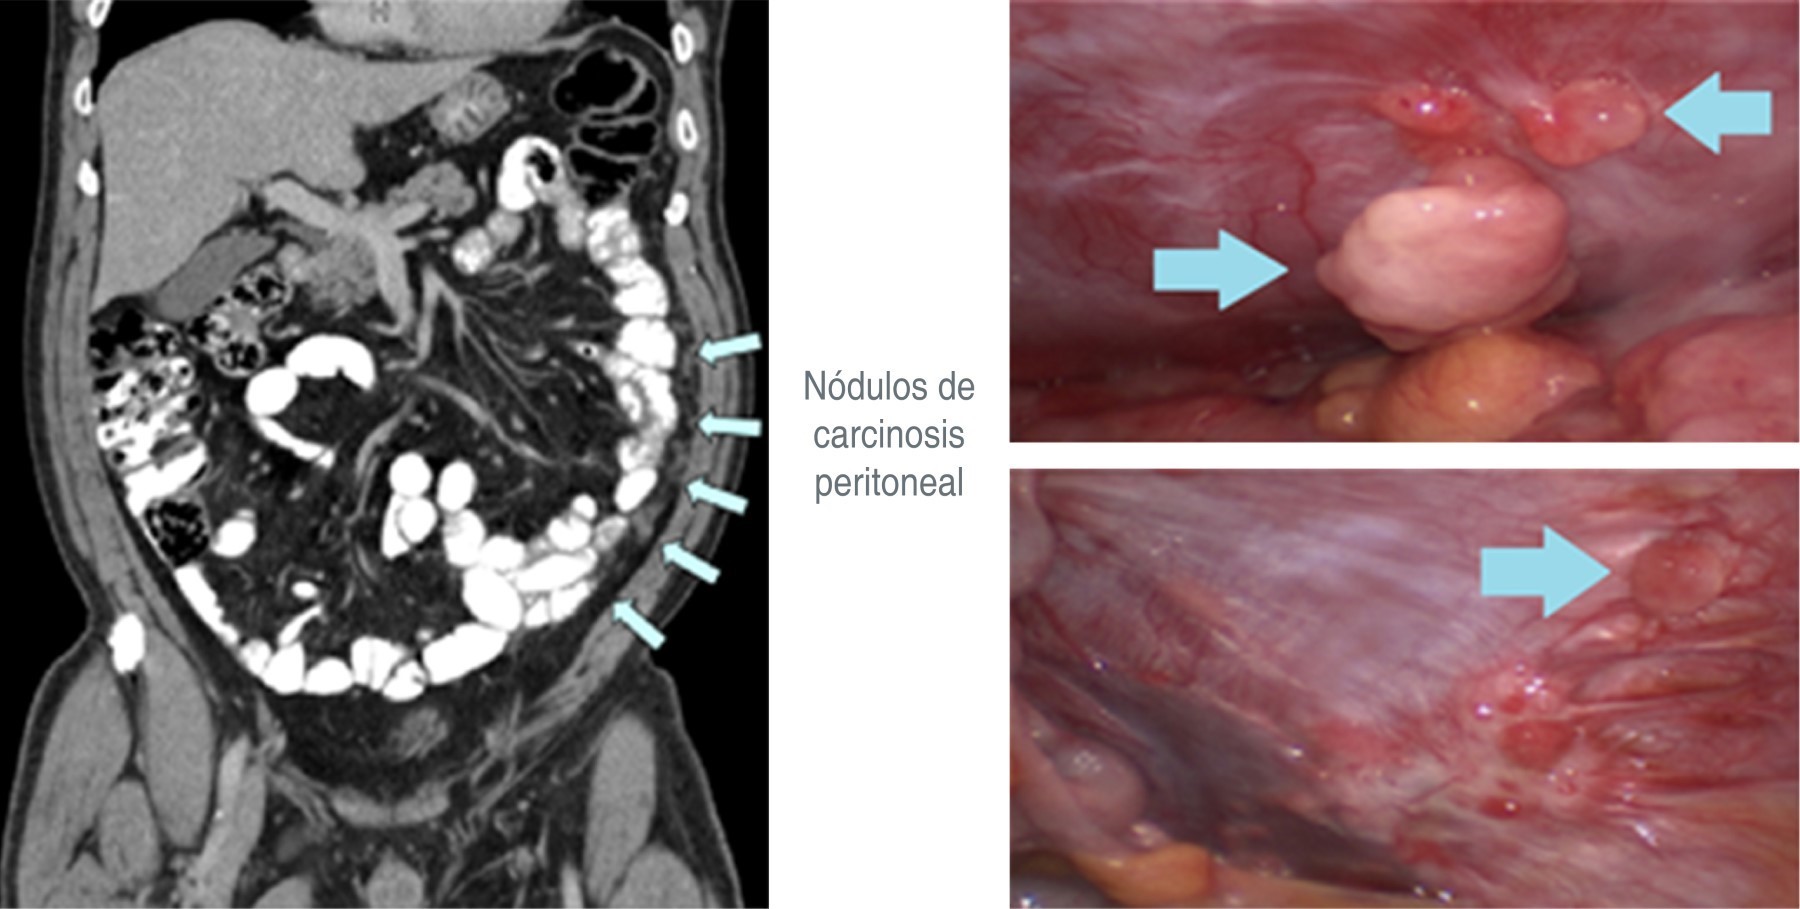

Así, la PIPAC puede ser realizada en aquellos casos con enfermedad estabilizada por la quimioterapia sistémica, pero que no permite acceder a la citorreducción debido al compromiso metastásico extenso (imposibilidad de llegar a una citorreducción completa) (Figura 2). Por otra parte, la PIPAC puede proponerse a los enfermos que no califican para una citorreducción con o sin HIPEC (Hyperthermic IntraPeritoneal Chemotherapy), o aquellos pacientes que quisiesen discontinuar la quimioterapia endovenosa.12-17

Figura 2